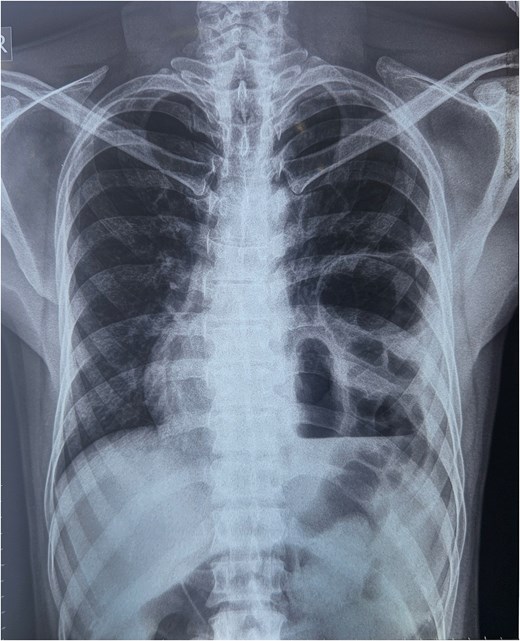

A chest x-ray was done, and it showed continuous internal air columns with abdominal gases, with a shifting of cardiac shadow to the contralateral side (Fig. 1). After stabilization of the patient, CECT thorax, abdomen, and pelvis was done which suggests left-sided diaphragmatic hernia with a defect of 28 mm with herniation of splenic flexure, entire left hemithorax. Obstructed loop seen within the herniated content with collapsed exiting loop s/o obstructed diaphragmatic hernia which led to mediastinal shift to right side and collapse of left lung (Fig. 2).